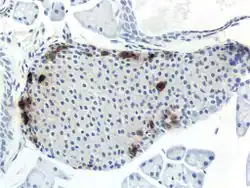

The pancreas serves multiple roles within mammalian organisms. It plays a role in the digestive system and the endocrine system making it an organ and a very important gland.[2] PP cells tend to located in the pancreatic islets, and are one of the rarer pancreatic cell types.[1] Some small clusters may also be found surrounded by exocrine pancreas.[3] They tend to be located in the duodenal part of the pancreas more medially.[3] Given their location in pancreatic islets along with their low population, they are able to respond efficiently to changes in blood sugar, nerve impulses, and chemical signaling through gap junctions or cellular signaling. PP cells show the highest concentration at the head of the pancreas.[1]

Through different microscopy techniques, the structural related details of PP cells have been able to be better understood. This is inclusive of how big they are, what their cellular membranes look like, the proteins associated with them, and even their size. PP cells are elongated cells. Another one of these details can be noted in insulins secretory granules, or container like buds, that store insulin within a cell. In PP cells, the size of the insulin granules are smaller and spherical and similar to those in alpha cells. This is noted in human PP cells, but different animals have been shown to have different sized granules compared to humans, like rodents. In cats and dogs, PP cells have large granules.[6] In rats, PP cells have few granules, similar to humans. In dogs, some PP cells are located in the walls of the antrum of the stomach.[3]